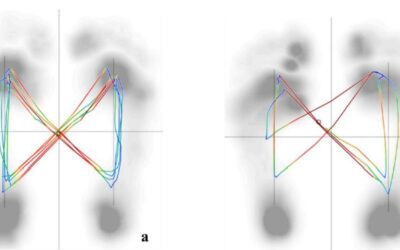

Plantar Pressure As Tool For Assessing Risk of Scoliosis

Idiopathic scoliosis (IS) caused by an unknown etiology is prevalent in...